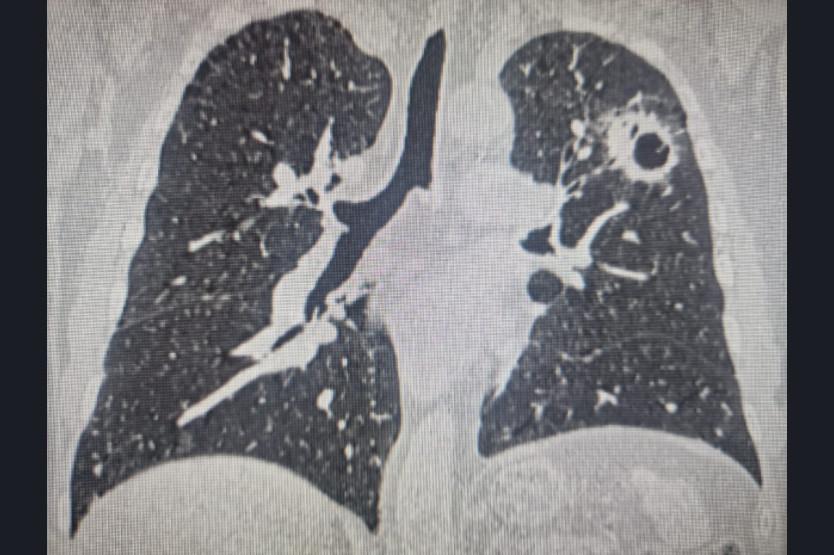

В первый раз сибиряку потребовалась помощь онкологов три года назад, тогда специалисты Новосибирского онкологического диспансера диагностировали у него центральный рак правого легкого. Обычно в таких случаях проводят пульмонэктомию, то есть удаляют легкое полностью.

Но в онкодиспансере решили сделать органосохраняющую операцию: удалили часть легкого с резекцией бронхов и сосудов, а после здоровые части органа сшили между между собой.

Первая операция позволила сохранить две трети легкого. Казалось бы, самое сложное позади. Врачи год пристально наблюдали за пациентом, что помогло вовремя выявить второй случай рака.

«Опухоль у мужчины развилась и в левом легком. Это были не метастазы после первого случая. Благодаря исследованиям вторую локализацию рака выявили на очень ранней стадии. В первый раз мы сохранили пациенту правое легкое, поэтому у бригады была возможность оперировать на левом», — говорит Вадим Козлов.

Выполнить операцию, когда у человека только одно легкое, невозможно, ведь во время процесса орган «отключат», пациенту станет нечем дышать. Однако правое легкое у мужчины функционировало, поэтому онкологи смогли провести вмешательство на левом.

Первая операция проводилась традиционным способом, обеспечивающим открытый доступ. Удаление сегмента второго легкого делали эндоскопически.